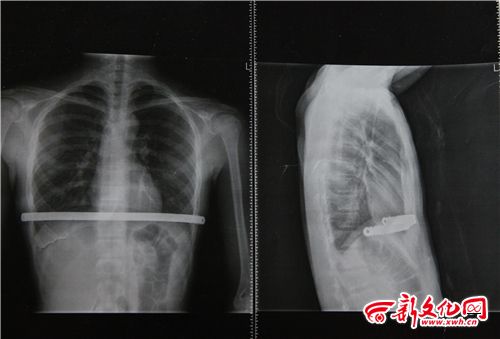

小博術(shù)后拍的CT片 本組圖片 新文化報(bào) 史磊 攝

家人懷疑小博的高燒與今年二月做的手術(shù)有關(guān),因?yàn)榛加新┒沸?,小博做手術(shù)在體內(nèi)植入了鋼板。家人帶小博到北京的醫(yī)院檢查,檢查結(jié)果顯示各項(xiàng)指標(biāo)都正常,不能確定小博高燒與之前的手術(shù)有關(guān)。